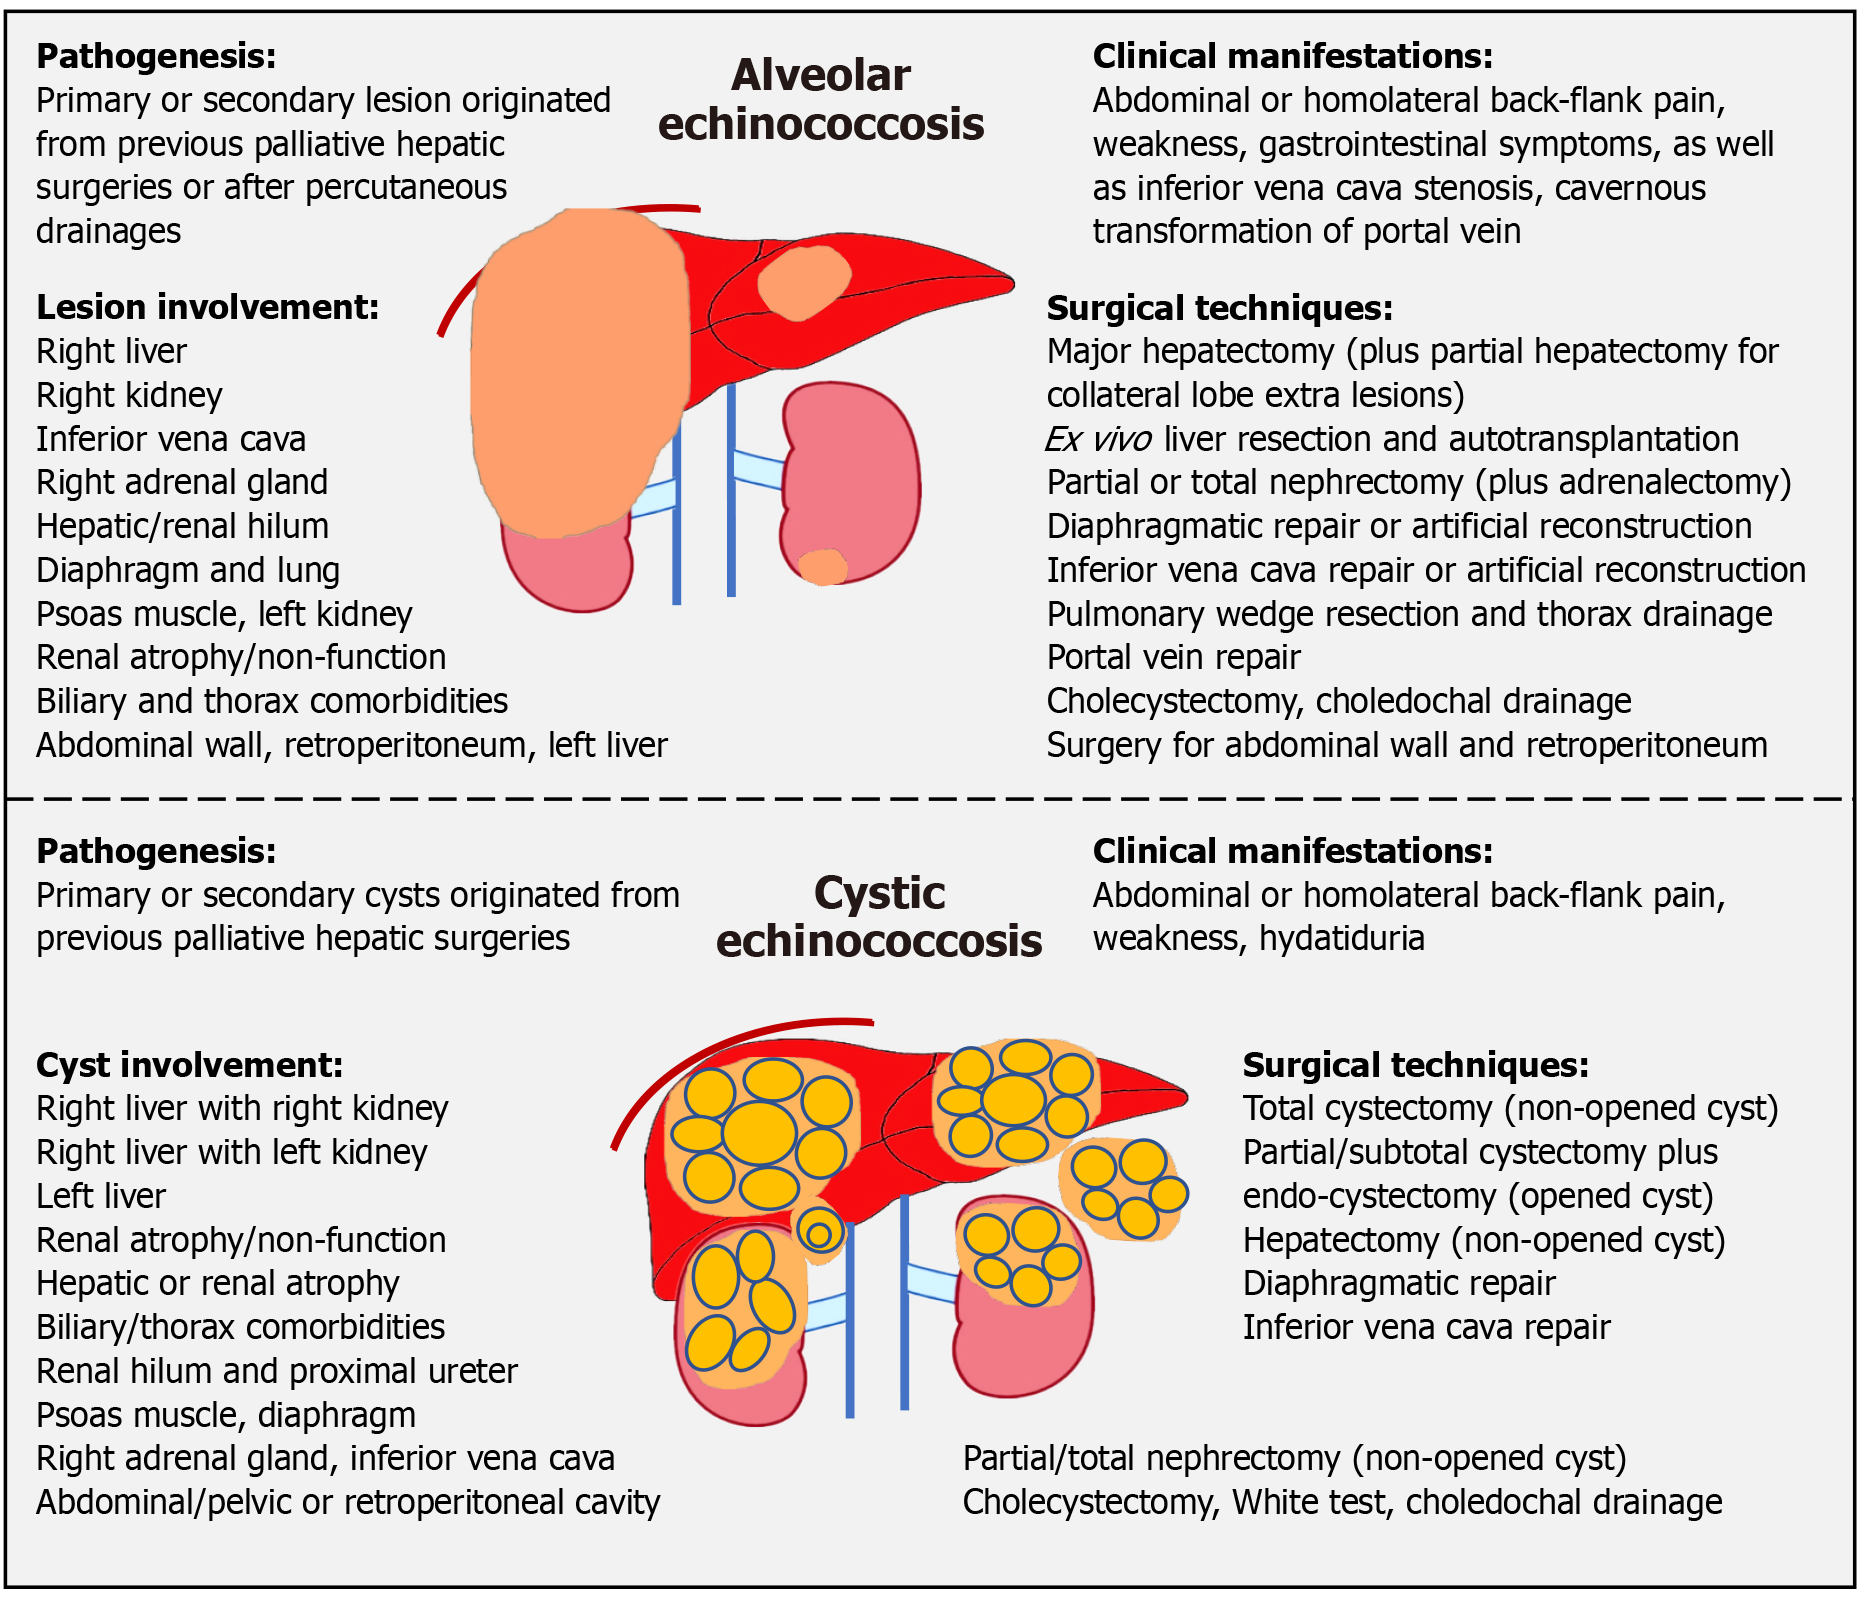

Figure 3 Study summary.

The upper and lower panels depict the pathogenesis, clinical manifestations, lesion/cyst involvement, and corresponding surgical techniques for alveolar echinococcosis and cystic echinococcosis patients, respectively.